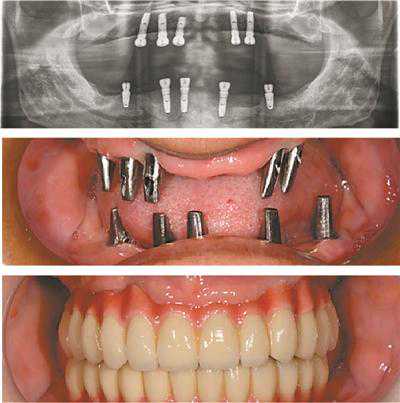

林老伯今年73岁,全口缺牙已十年,因牙周病严重、牙槽骨不足,曾7次想种牙均未果,只能选择戴活动假牙维持咀嚼功能。近期,林伯看到DMD国际化种植牙救助中心关于P3I牙周数位精准种植技术的资讯后,再次来到梅里奥口腔咨询。哈佛齿科博士团专家对其缺牙问题进行了联合会诊,制定了P3I+ALL-on-N的种植方案,首先采用亲水激光进行牙周治疗,远期预防控制种植体炎症,确保种植体与牙槽骨紧密结合,再通过ALL-on-N即刻种植技术,上颌种5颗植体修复14颗牙,下颌种5颗修复半口牙,不仅实现了种牙愿望,更节省了近半费用。